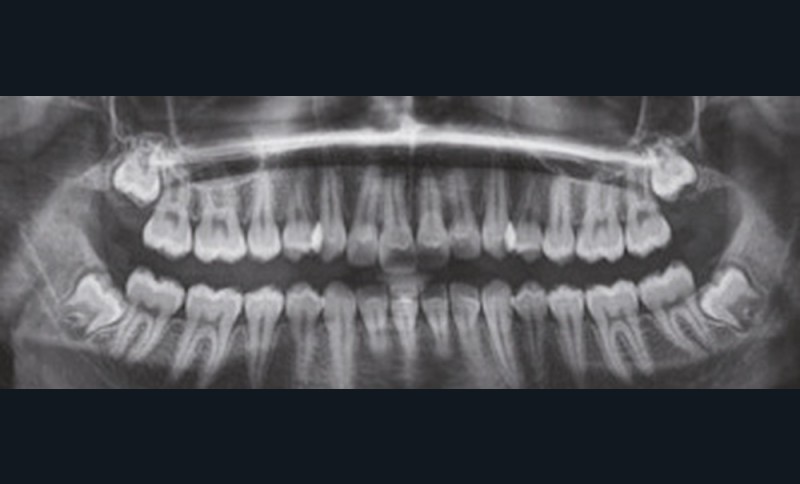

Examen clinique (fig. 1 à 7)

À la vue de l’examen radiographique, elle est au stade CS6 d’après la méthode de maturation vertébrale de Baccetti [1]. Elle présente une classe II squelettique de Ballard par rétrognathie mandibulaire avec un ANB de 9° et un AoBo de 9 mm sur un schéma facial normo-divergent. L’incisive mandibulaire est vestibulo-versée (IMPA = 114°). Le maxillaire est bien positionné. Elle présente de plus une dysharmonie dento-dentaire (DDD) antérieure par excès mandibulaire.